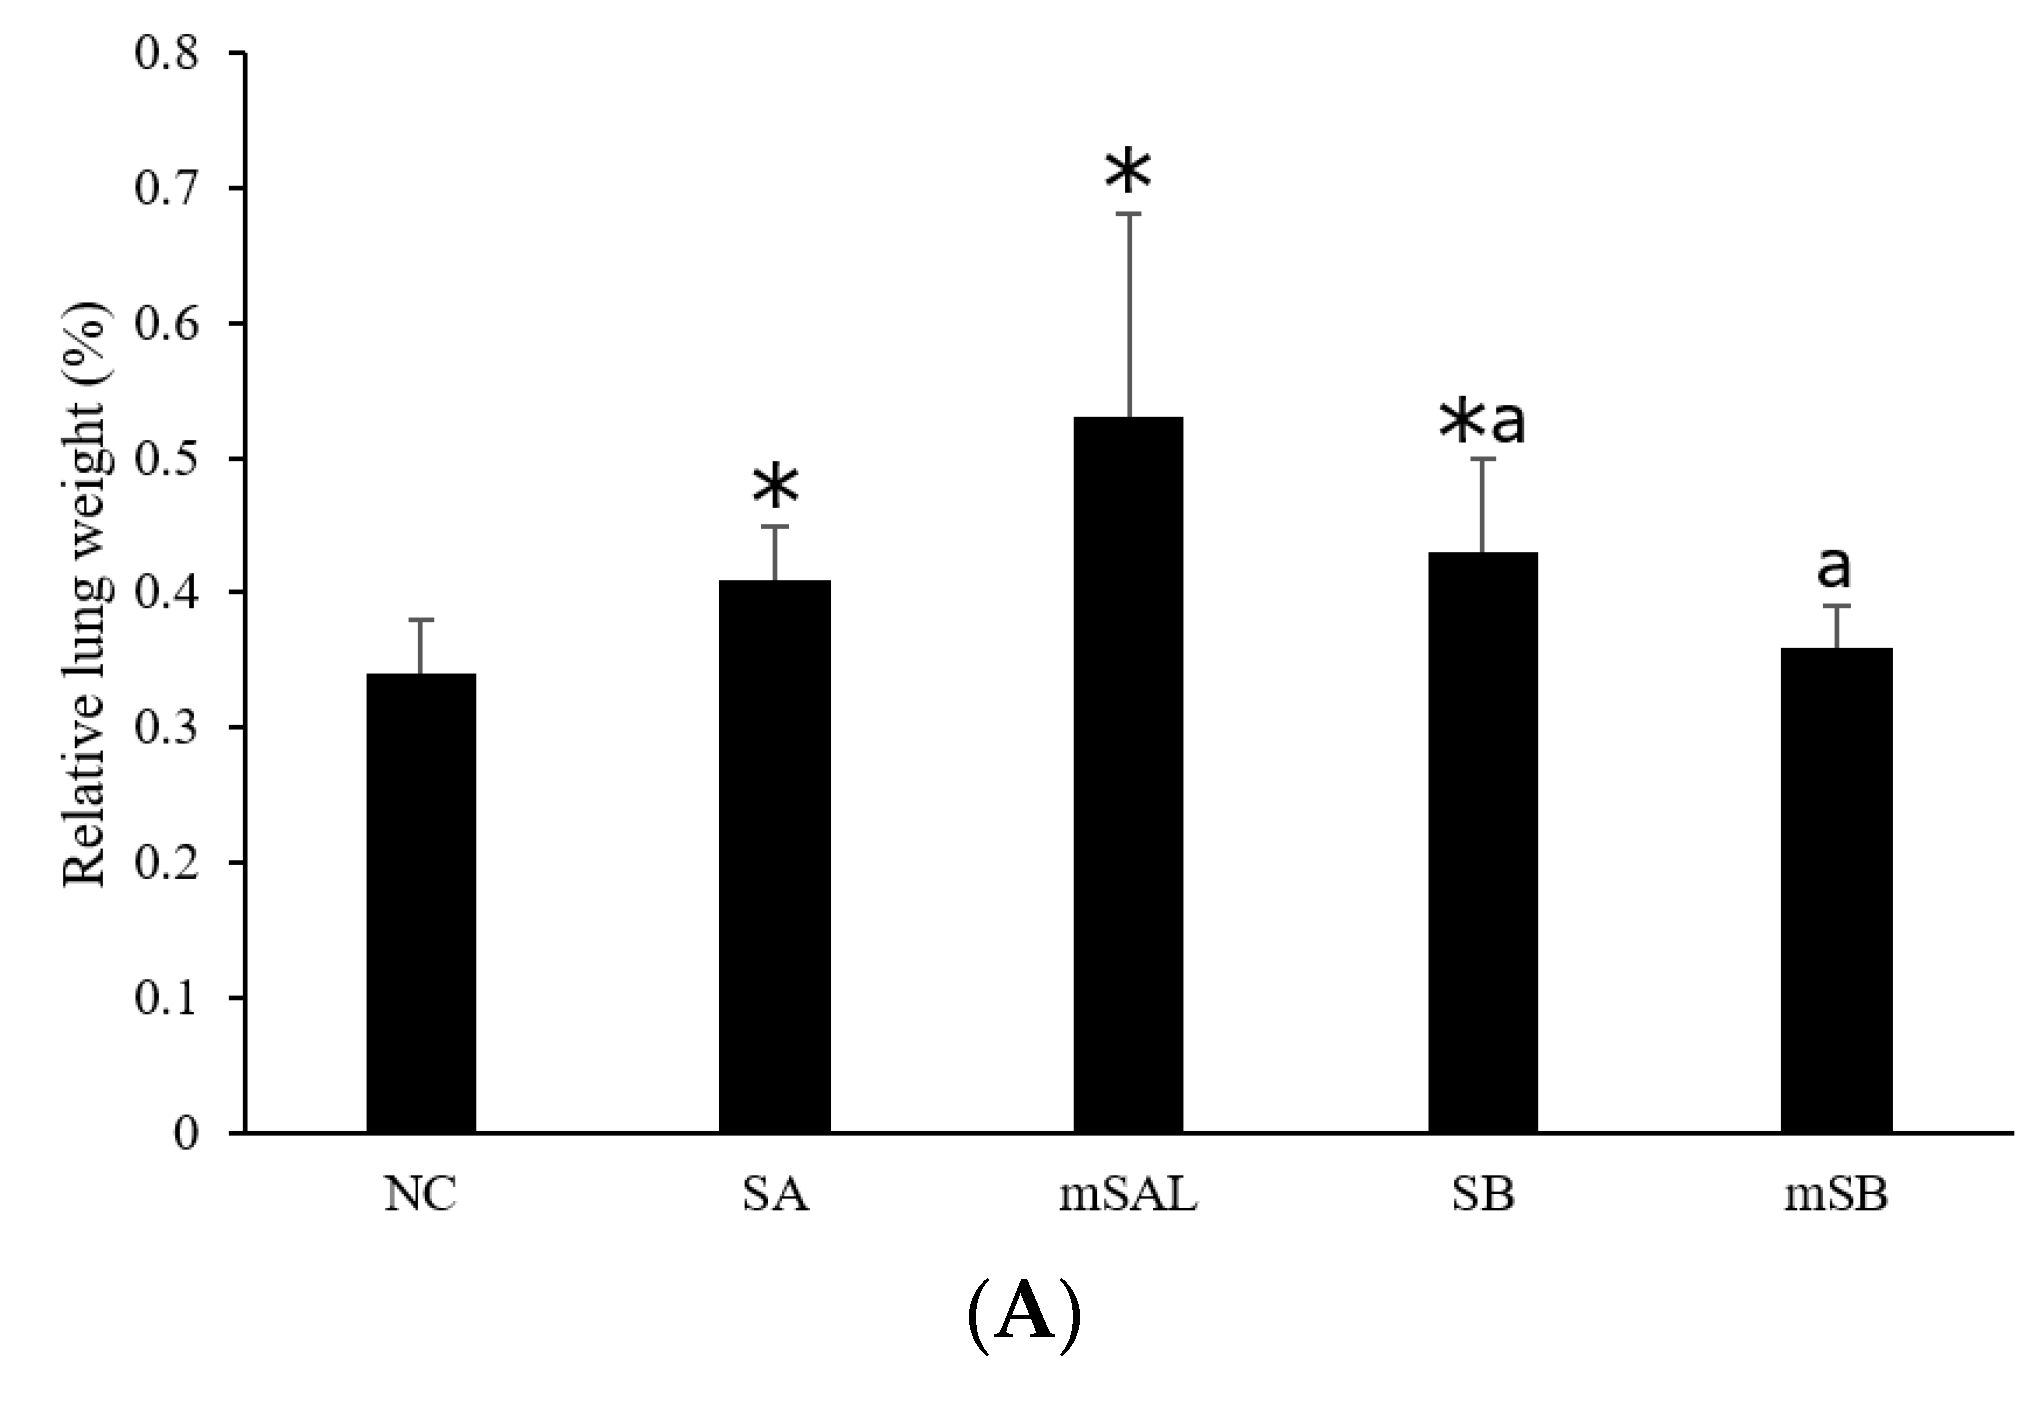

3.4. Acute Pulmonary Toxicity Test (1 D)

3.5. Acute Pulmonary Toxicity Test (14 D)

| Group | WBC 2 (105) | E (105) | N (105) | L (105) | M (105) |

|---|---|---|---|---|---|

| NC 1 | 6.1 ± 2.9 3 | 0.0 ± 0.0 | 0.1 ± 0.1 | 0.3 ± 0.2 | 5.7 ± 2.7 |

| SA | 23.7 ± 12.2 *,a | 0.4 ± 1.0 | 10.1 ± 8.1 * | 1.1 ± 0.7 * | 12.2 ± 3.9 * |

| mSAL | 39.0 ± 10.8 *,a | 0.6 ± 0.7 | 20.4 ± 7.9 * | 2.0 ± 1.3 * | 16.1 ± 10.0 * |

| SB | 33.5 ± 19.2 *,b | 0.4 ± 0.4 * | 15.6 ± 14.0 *,b | 2.2 ± 1.4 *,b | 15.3 ± 6.5 * |

| mSB | 10.7 ± 10.7 b | 0.1 ± 0.2 | 0.8 ± 1.5 b | 0.5 ± 0.5 b | 9.4 ± 8.7 |